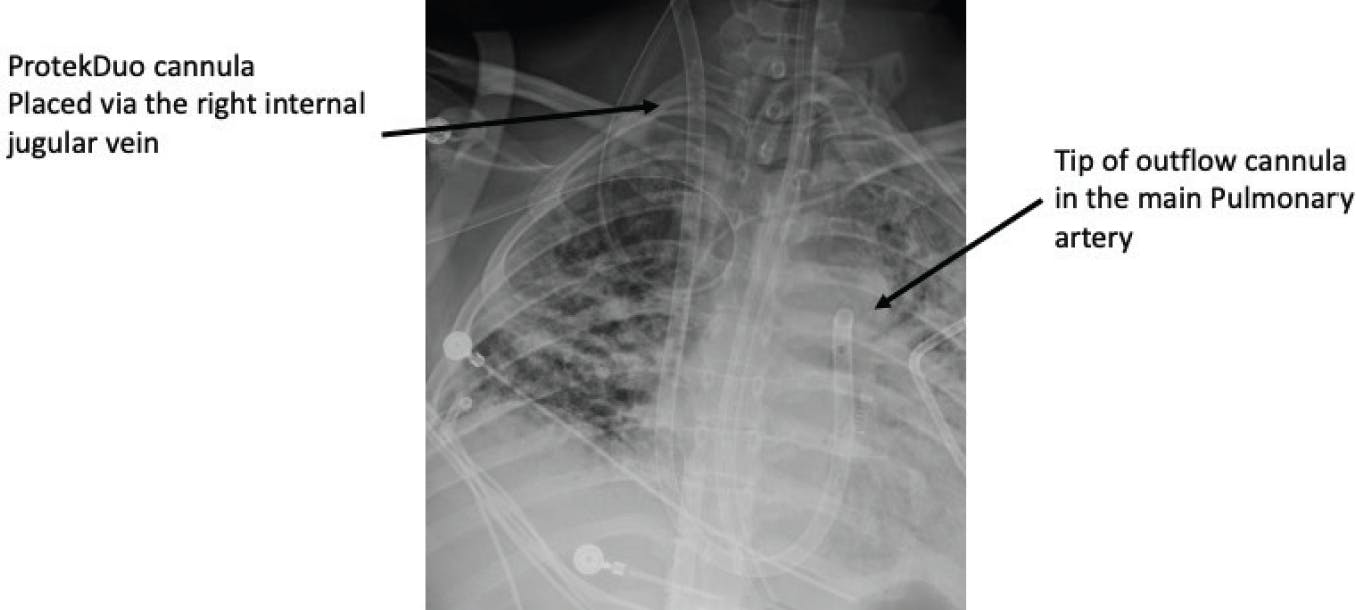

The ProtekDuo is a 29- or 31-F dual-lumen catheter placed via the internal jugular vein into the pulmonary artery. The inflow cannula in the right atrium removes blood from the body, where an external pump then ejects the blood through the outflow lumen to the pulmonary artery. Because the pump is external to the body, an oxygenator can be easily added before blood is returned to the pulmonary artery. Similar to the Impella RP device, use seems to be best in patients with residual RV failure after there has been clot reduction in the pulmonary arteries. Small case series have been published but large-scale studies in PE have not been performed.23 Figure 5 illustrates the ProtekDuo system.

Figure 5. Example of a ProtekDuo device placed via the right internal jugular vein into the pulmonary artery.